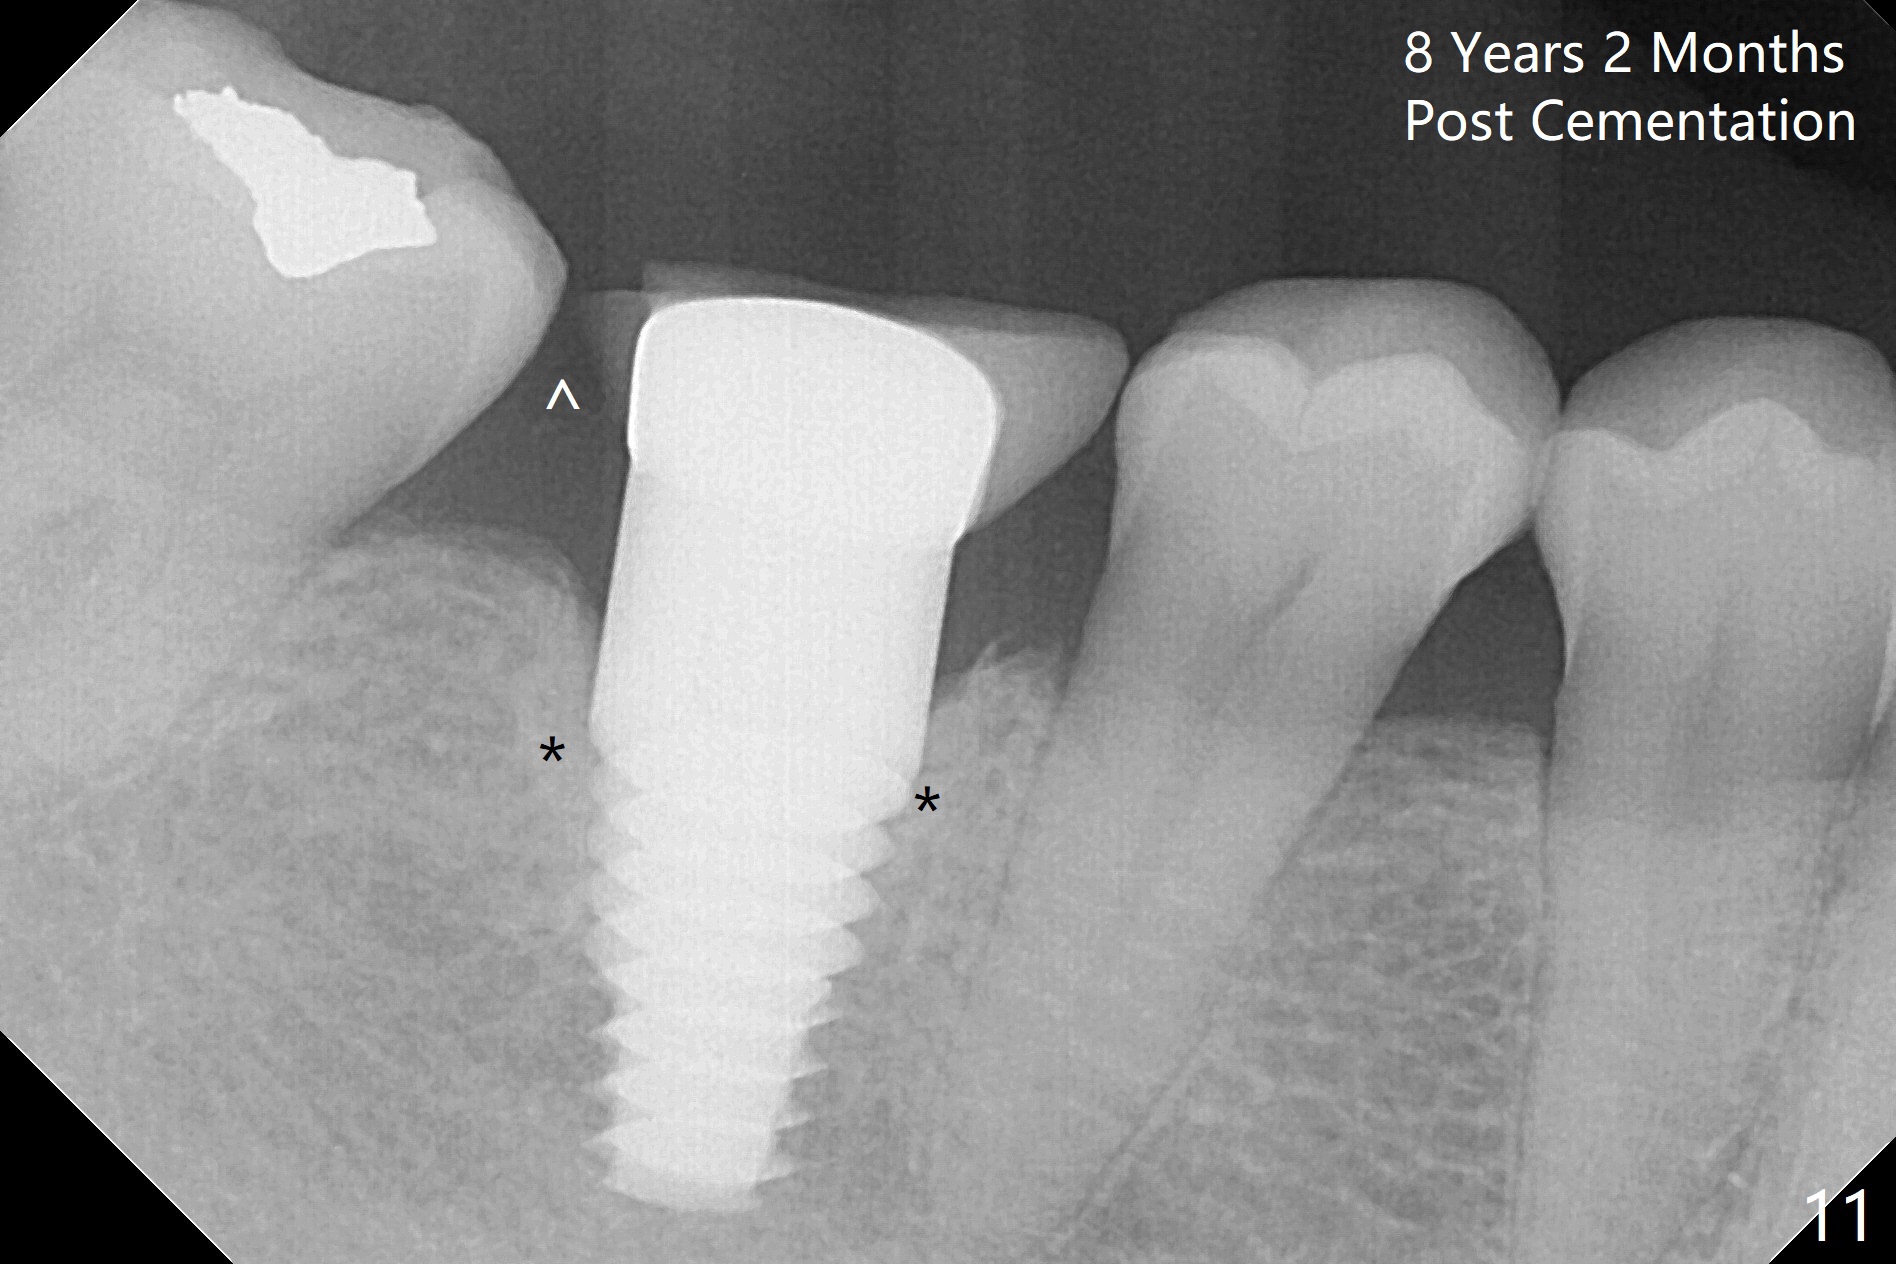

Metal exposure of the PFM crown (Fig.5,8) is associated with supraeruption of the opposing tooth (Fig.10 arrow). Increased bone density around the coronal portion of the implant 8 years 2 months post cementation (Fig.11 *) suggests bruxism, which is related to distal marginal porcelain chip (^). There is no food impaction with a new crown (Fig.12).